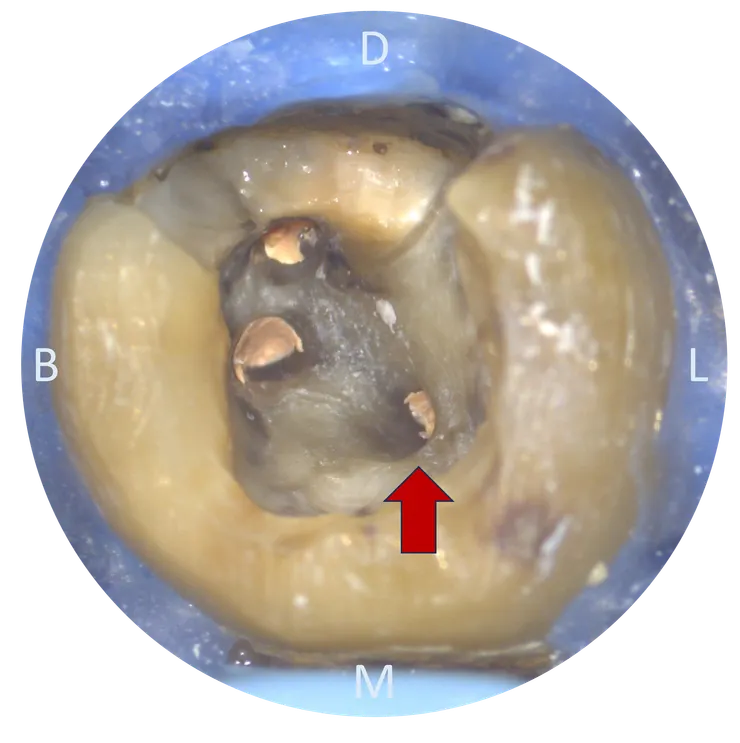

把 CBCT 的資訊記在腦中後,我們轉移到顯微鏡下來看看實際的情況:

可以看到用了五年的 temporary crown 下已經養出了一推 caries......

先把 caries 挖乾淨後再開始 retreat.

這次主要 focus 在箭頭所指的 ML canal.

把舊 GP 大致移除後,幸運地在根管壁上看到一個突兀的洞 (紅色箭頭所指),剛好就位於原本路徑 (粉紅色箭頭) 的 DB side !

拿起 file 瞄準那個洞督進去 ---

(這輕描淡寫的一句話,真要在張口度受限的 37 ML canal 中段做到,其實相當相當不容易......)

就找到了真正的 ML canal pathway !

然後就完成了 C&S 並且 RCF.